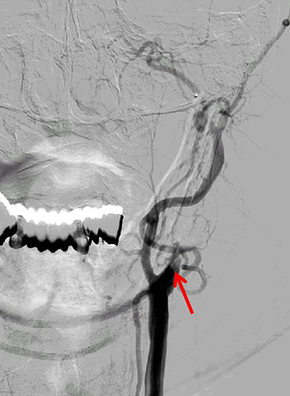

2. 혈전 제거술

<혈전 제거술>

- 혈전 용해술은 혈전을 녹여 뚫는 치료법으로 뇌혈관에 발생한 색전이나 혈전으로 혈액을 공급받지 못한 뇌 조직이 죽게 되므로 빠른 시간 안에 혈관을 재개통하여 뇌 조직의 손상을 최소화하는 것이 중요합니다.